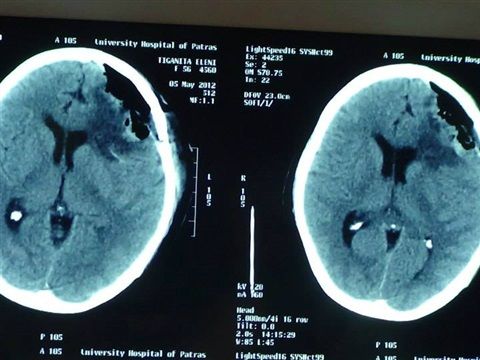

Removal of a large brain meningioma

Patient suffering from seizures and hemiparesis as a consequence of a giant brain meningioma.

Complete neurological recovery after total removal of the meningioma.